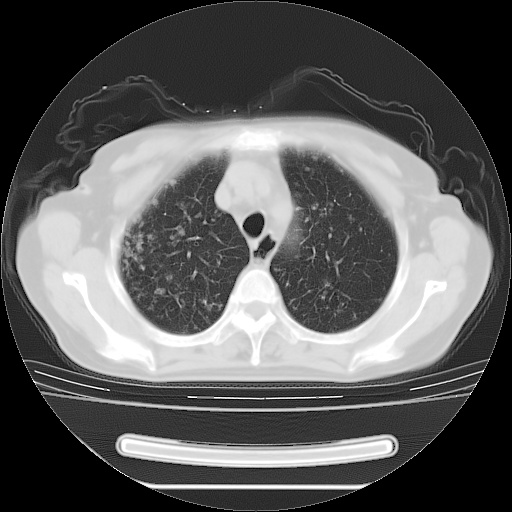

患者女性,72岁,慢性咳嗽3月余,曾抗炎治疗无效果,最近抗结核治疗约半月余,症状缓解。

ct示两肺粟粒状病灶,以两肺上叶尖后段及下叶背段分布为主;首先考虑结核。请战友们分析。

考虑 1 弥漫性泛细支气管炎, 2 结核不除外/.  有小叶中心结节 和 树芽征!!

两肺内病灶呈小结节状和树芽状,纵膈的肿大的淋巴结密度不均匀,并见有钙化,考虑为两肺结核可能更大些。

两肺内病灶呈小结节状和树芽状,纵膈的肿大的淋巴结密度不均匀,并见有钙化,多形态病灶,考虑为两肺结核,肝内考虑小囊肿。